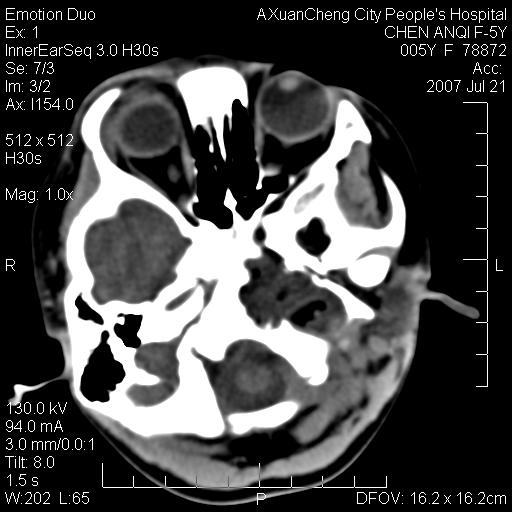

患儿5岁,左耳流脓痛疼一周,左外耳道肉芽组织填塞 软组织窗显示病灶内结节状低密度影为气体密度

1.左耳中耳炎. 2.考虑伴颅内感染.

颅底骨质破坏,建议增强扫描

左侧中耳炎并胆脂瘤,左颞骨岩部骨质破坏并颅内感染积气。